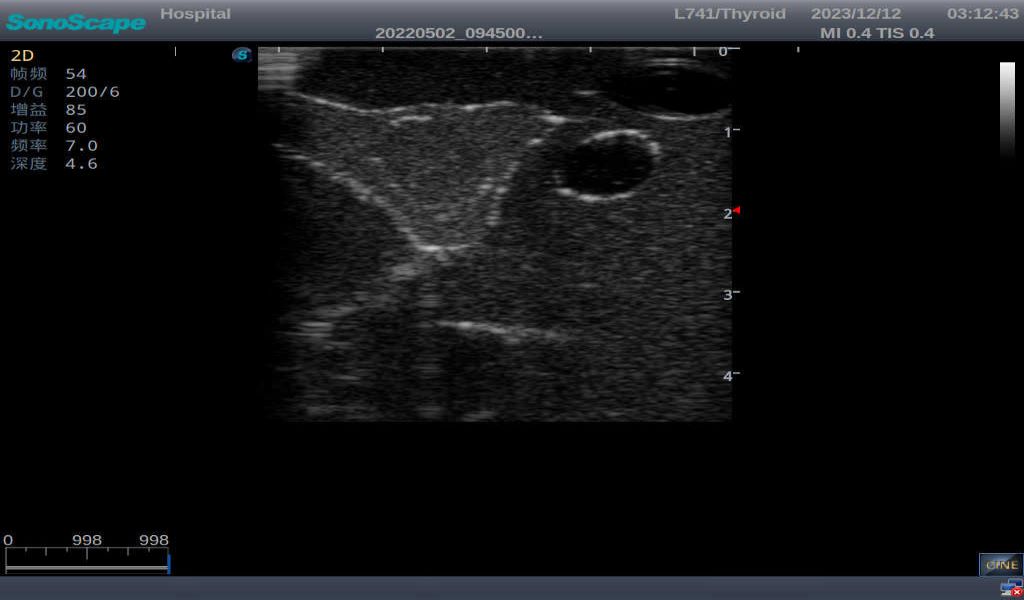

3)       It comes with four (4) thyroid modules and can show five (5) ultrasonic images: normal thyroid, thyroid adenoma, thyroid cancer, nodular goiter, thyroid cyst

Normal thyroid with homogeneous parenchymal echo and well-defined capsule

Thyroid cyst, which fluid area, dark and echo-free area can be seen